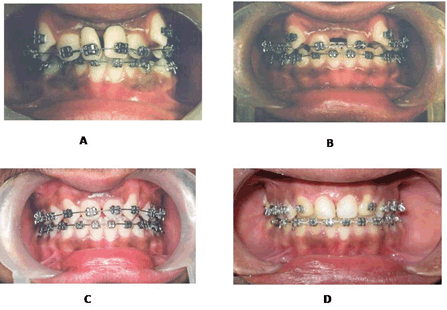

A 0.018" preadjusted edgewise appliance (Roth prescription) was used. During the initial alignment and leveling, prosthetic maxillary central incisors were attached to the arch wire at the extraction site (Figure 4A).These teeth were gradually reduced proximally so that by the end of alignment and leveling phase one artificial tooth was left, which was then removed. Space closure was done with 0.016x0.022 in stainless steel archwires and intramaxillary elastic chain (Figure 4B). The elastic chains were discontinued once well distributed spaces around the maxillary lateral incisors were achieved for later composite restoration of these teeth (Figure 4C).After that gingivectomy and composite restorations of the laterals were done to simulate them with the central incisors and the palatal surface and the cusp tip of canines was reduced to make it resemble lateral incisor (Figure 4D).

Figure 4: (A-D): Treatment progress photographs.